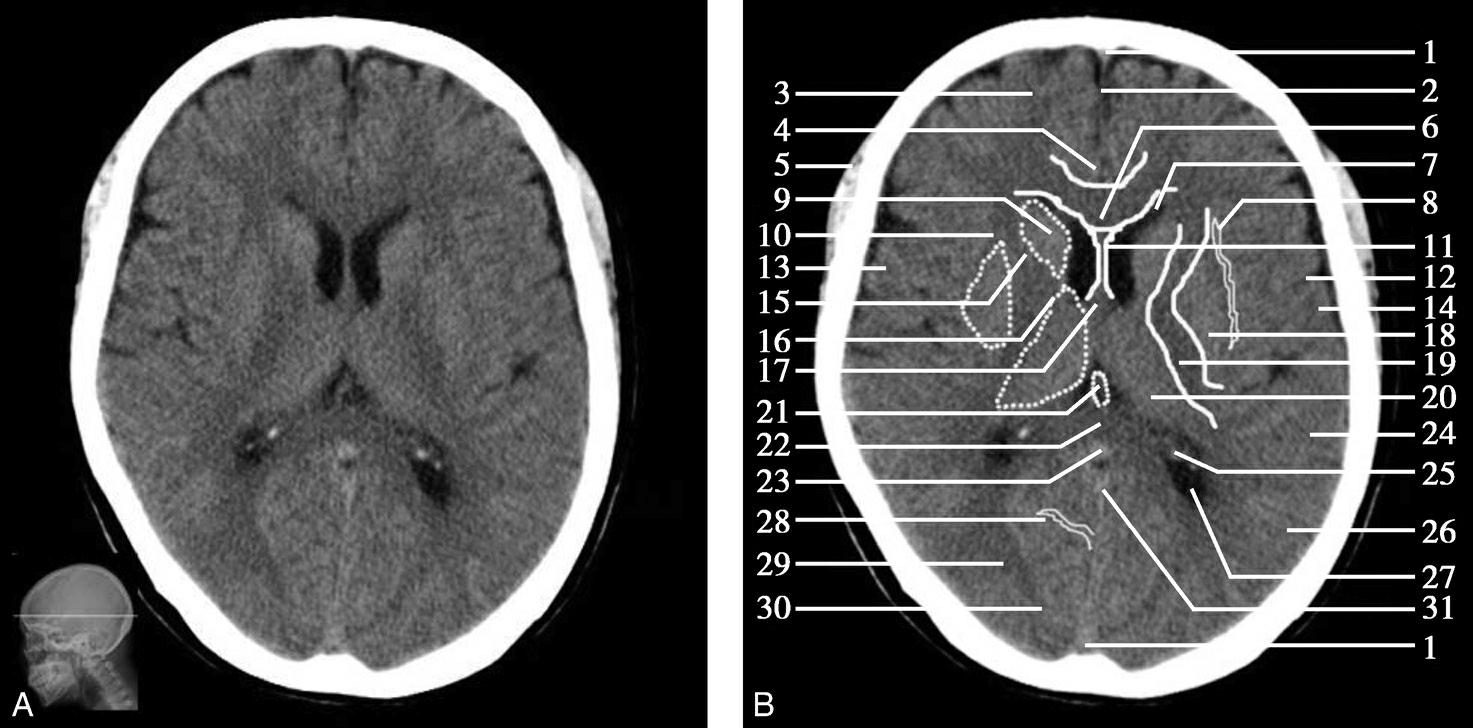

图1-2-29 基底节层面

A.横断面;B.横断面标注

1.上矢状窦;2.大脑镰;3.额叶;4.扣带回;5.颞肌;6.胼胝体膝部;7.侧脑室前角;8.岛叶;9.尾状核头部;10.外囊;11.透明隔;12.中央沟;13.中央前回;14.中央后回;15.内囊前肢;16.内囊膝部;17.穹窿柱;18.豆状核;19.内囊后肢;20.丘脑;21.大脑内静脉;22.胼胝体压部;23.大脑大静脉;24.颞叶;25.脉络膜丛;26.顶叶;27.侧脑室三角区;28.顶枕沟;29.视辐射;30.枕叶;31.直窦

双侧侧脑室前角呈倒“八”字形向前外方伸展,其前壁为胼胝体膝部、内侧壁为透明隔、外侧壁为尾状核头。透明隔后方与穹窿柱相连,穹窿柱与两侧背侧丘脑前部间为室间孔,沟通双侧侧脑室及第三脑室。第三脑室居双侧背侧丘脑间,呈纵向走行的裂隙状。尾状核头与背侧丘脑的外侧为“> <”形的内囊,由前肢、膝及后肢三部分组成,内囊与额盖、顶盖之间,由内侧向外侧依次为豆状核、外囊、屏状核、最外囊、岛叶及外侧裂。枕叶与顶叶分界为顶枕沟,此沟在胼胝体压部层面显示最佳。胼胝体压部外侧有侧脑室三角区,内有脉络丛,常见钙化。大脑半球内侧面前部可见额内侧回和扣带回,后部可见扣带回和舌回。

顶枕沟位于胼胝体之后,是半球内侧面的一条较深的沟,此沟后方及大脑镰两侧为枕叶,为顶枕叶的分界标志。外侧裂池位于半球凸面的中点处,并向内、向后延伸,可作为额、颞叶的分界标志。此层面同时出现大脑半球的额、颞、顶、枕4个叶。

基底节为脑卒中的好发部位,与纹状动脉的解剖特点有关,深穿支动脉的破裂和栓塞可分别引起基底节区的出血和梗死(图1-2-32、图1-2-33)。